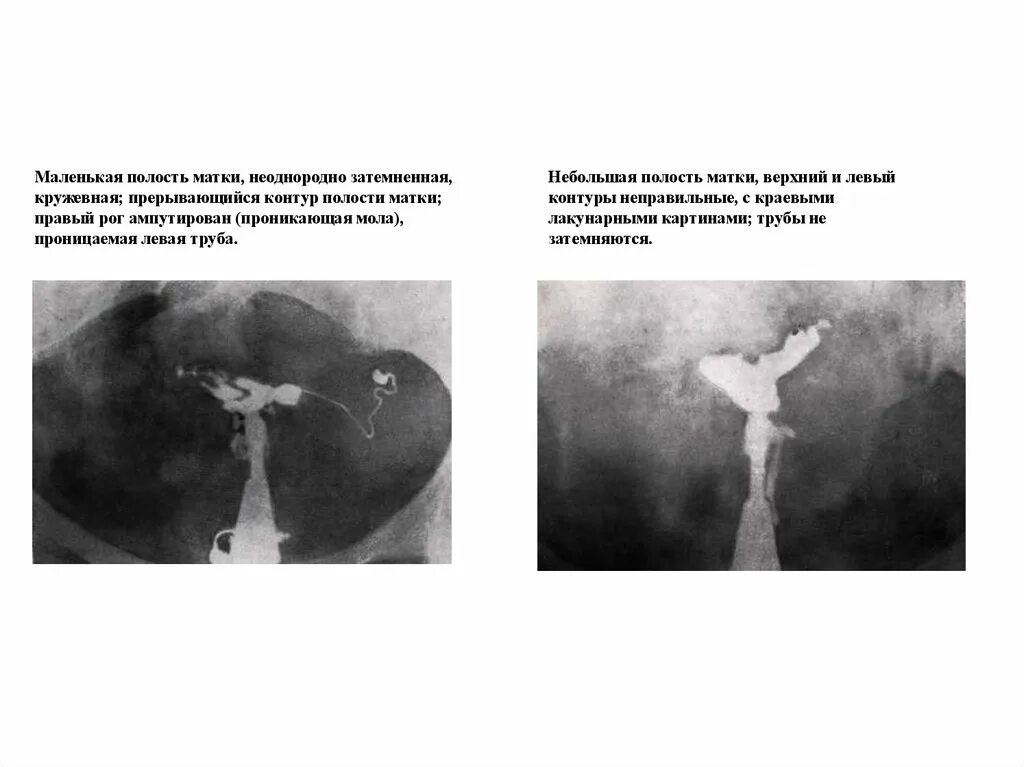

Матка увеличена причины при осмотре у гинеколога